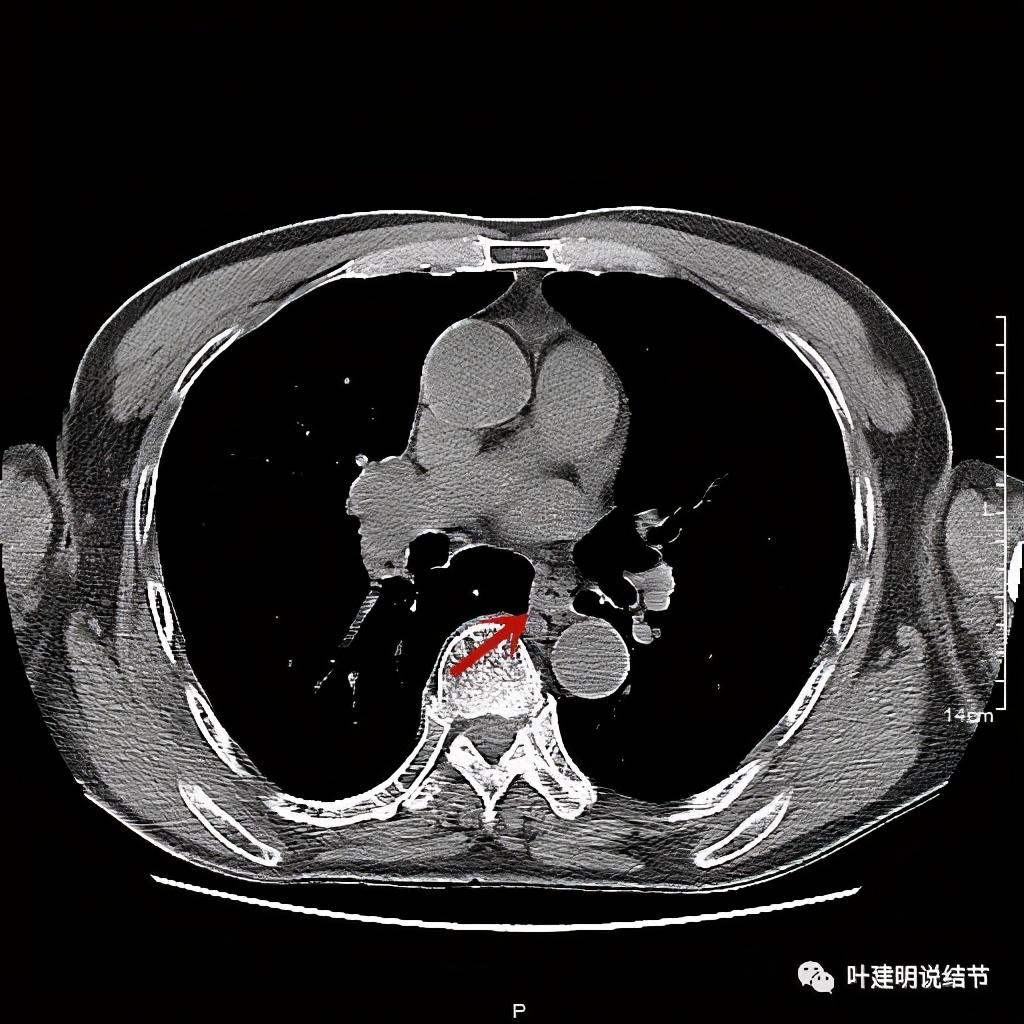

活检后食管是鳞癌,结肠是腺癌。下面是其术前CT的图像:

食管壁开始增厚

肿瘤已经较明显

位于左下肺静脉水平

红色示肿瘤